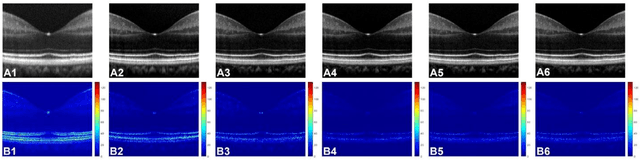

Abstract:Chromatic dispersion is a common problem to degrade the system resolution in optical coherence tomography (OCT). This study is to develop a deep learning network for automated dispersion compensation (ADC-Net) in OCT. The ADC-Net is based on a redesigned UNet architecture which employs an encoder-decoder pipeline. The input section encompasses partially compensated OCT B-scans with individual retinal layers optimized. Corresponding output is a fully compensated OCT B-scans with all retinal layers optimized. Two numeric parameters, i.e., peak signal to noise ratio (PSNR) and structural similarity index metric computed at multiple scales (MS-SSIM), were used for objective assessment of the ADC-Net performance. Comparative analysis of training models, including single, three, five, seven and nine input channels were implemented. The five-input channels implementation was observed as the optimal mode for ADC-Net training to achieve robust dispersion compensation in OCT